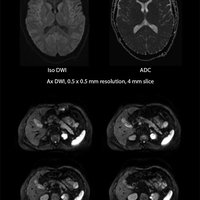

KI-optimiertes Arbeiten und modernste 3T-Technologie machen den Vantage Galan 3T von Canon Medical aus. Canons KI-Anwendung AiCE, kurz für Advanced intelligent Clear-Imagequality Engine, entfernt intelligent das Rauschen und führt zu einer Verbesserung des SNR (Signal-Rausch-Verhältnis). Mit Hilfe der Deep Learning Technologie gelingen besonders klare und deutliche Bilder. Insgesamt ermöglicht die KI-Unterstützung des Vantage Galan 3T somit nicht nur eine höhere Auflösung der Bilder, sondern verkürzt in vielen Fällen auch die Aufnahmezeit.

Mit der PURERF-Technologie und der PUREGradienten-Technologie werden das SNR um bis zu 20% verbessert und Diffusionsbilder optimiert.

• MultiBand SPEEDER beschleunigt Aufnahmedauer hochaufgelöster Diffusionsbilder